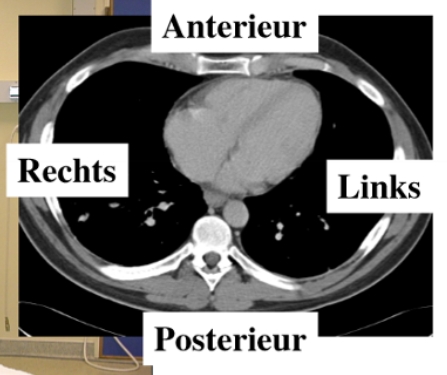

CT-scan

maakt dwarse doorsneden van de mens → salami

longen + ribben

in het midden: mediastinum

= structuren tussen de longen (bv. ook het hart)